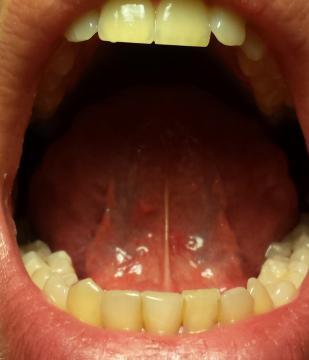

Chcem sa vas opytat ci vidite nieco na jazyku co by tam nemalo byt. Ďakujem :)

Takto sa to na 100% posúdiť rozhodne nedá, ale čo je vidieť z fotky, tak je všetko normálne. Máte výslovne nejaká zdravotné problémy?